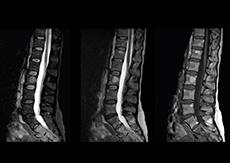

More information without extending time slot

“In our lumbar spine MRI, the value of mDIXON TSE is so obvious. Normally we perform T1 and T2 scans in sagittal and transverse orientation.It used to take too much time to add a sagittal T2 with good fat suppression.But now, using mDIXON TSE, we get the sagittal T2 fat suppressed images ‘for free’, that is: without adding time.” “Diagnostically that is a great benefit. I sometimes see abnormalities in the fat suppressed sagittal T2 that would be quite challenging to notice in the T2 without fat suppression. There have been several diagnoses that I could make easier because of our exam setup with mDIXON TSE, such as sacrum insufficiency fractures and sacroileitis; these were more challenging with our previous exam setup.”